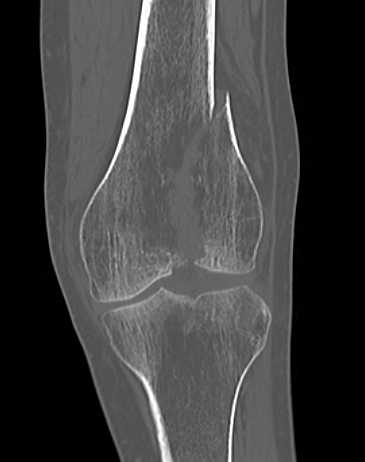

Xray / CT

Options

Dual Plate

Plate + Retrograde nail

Distal femur replacement

Indications

Significant comminution

Loss of medial cortical buttress